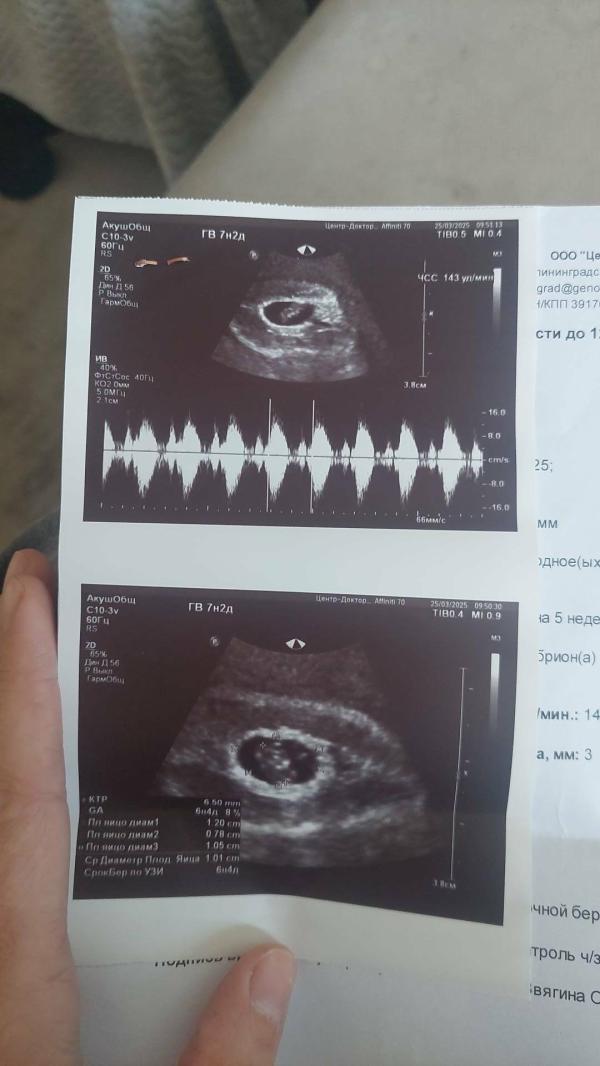

Через не делю в другом месте помериди пя 12 мм и ктр 6.5 мм(2фото) и говорят что плодное яйцо отстаёт по сроку и исход 50 на 50